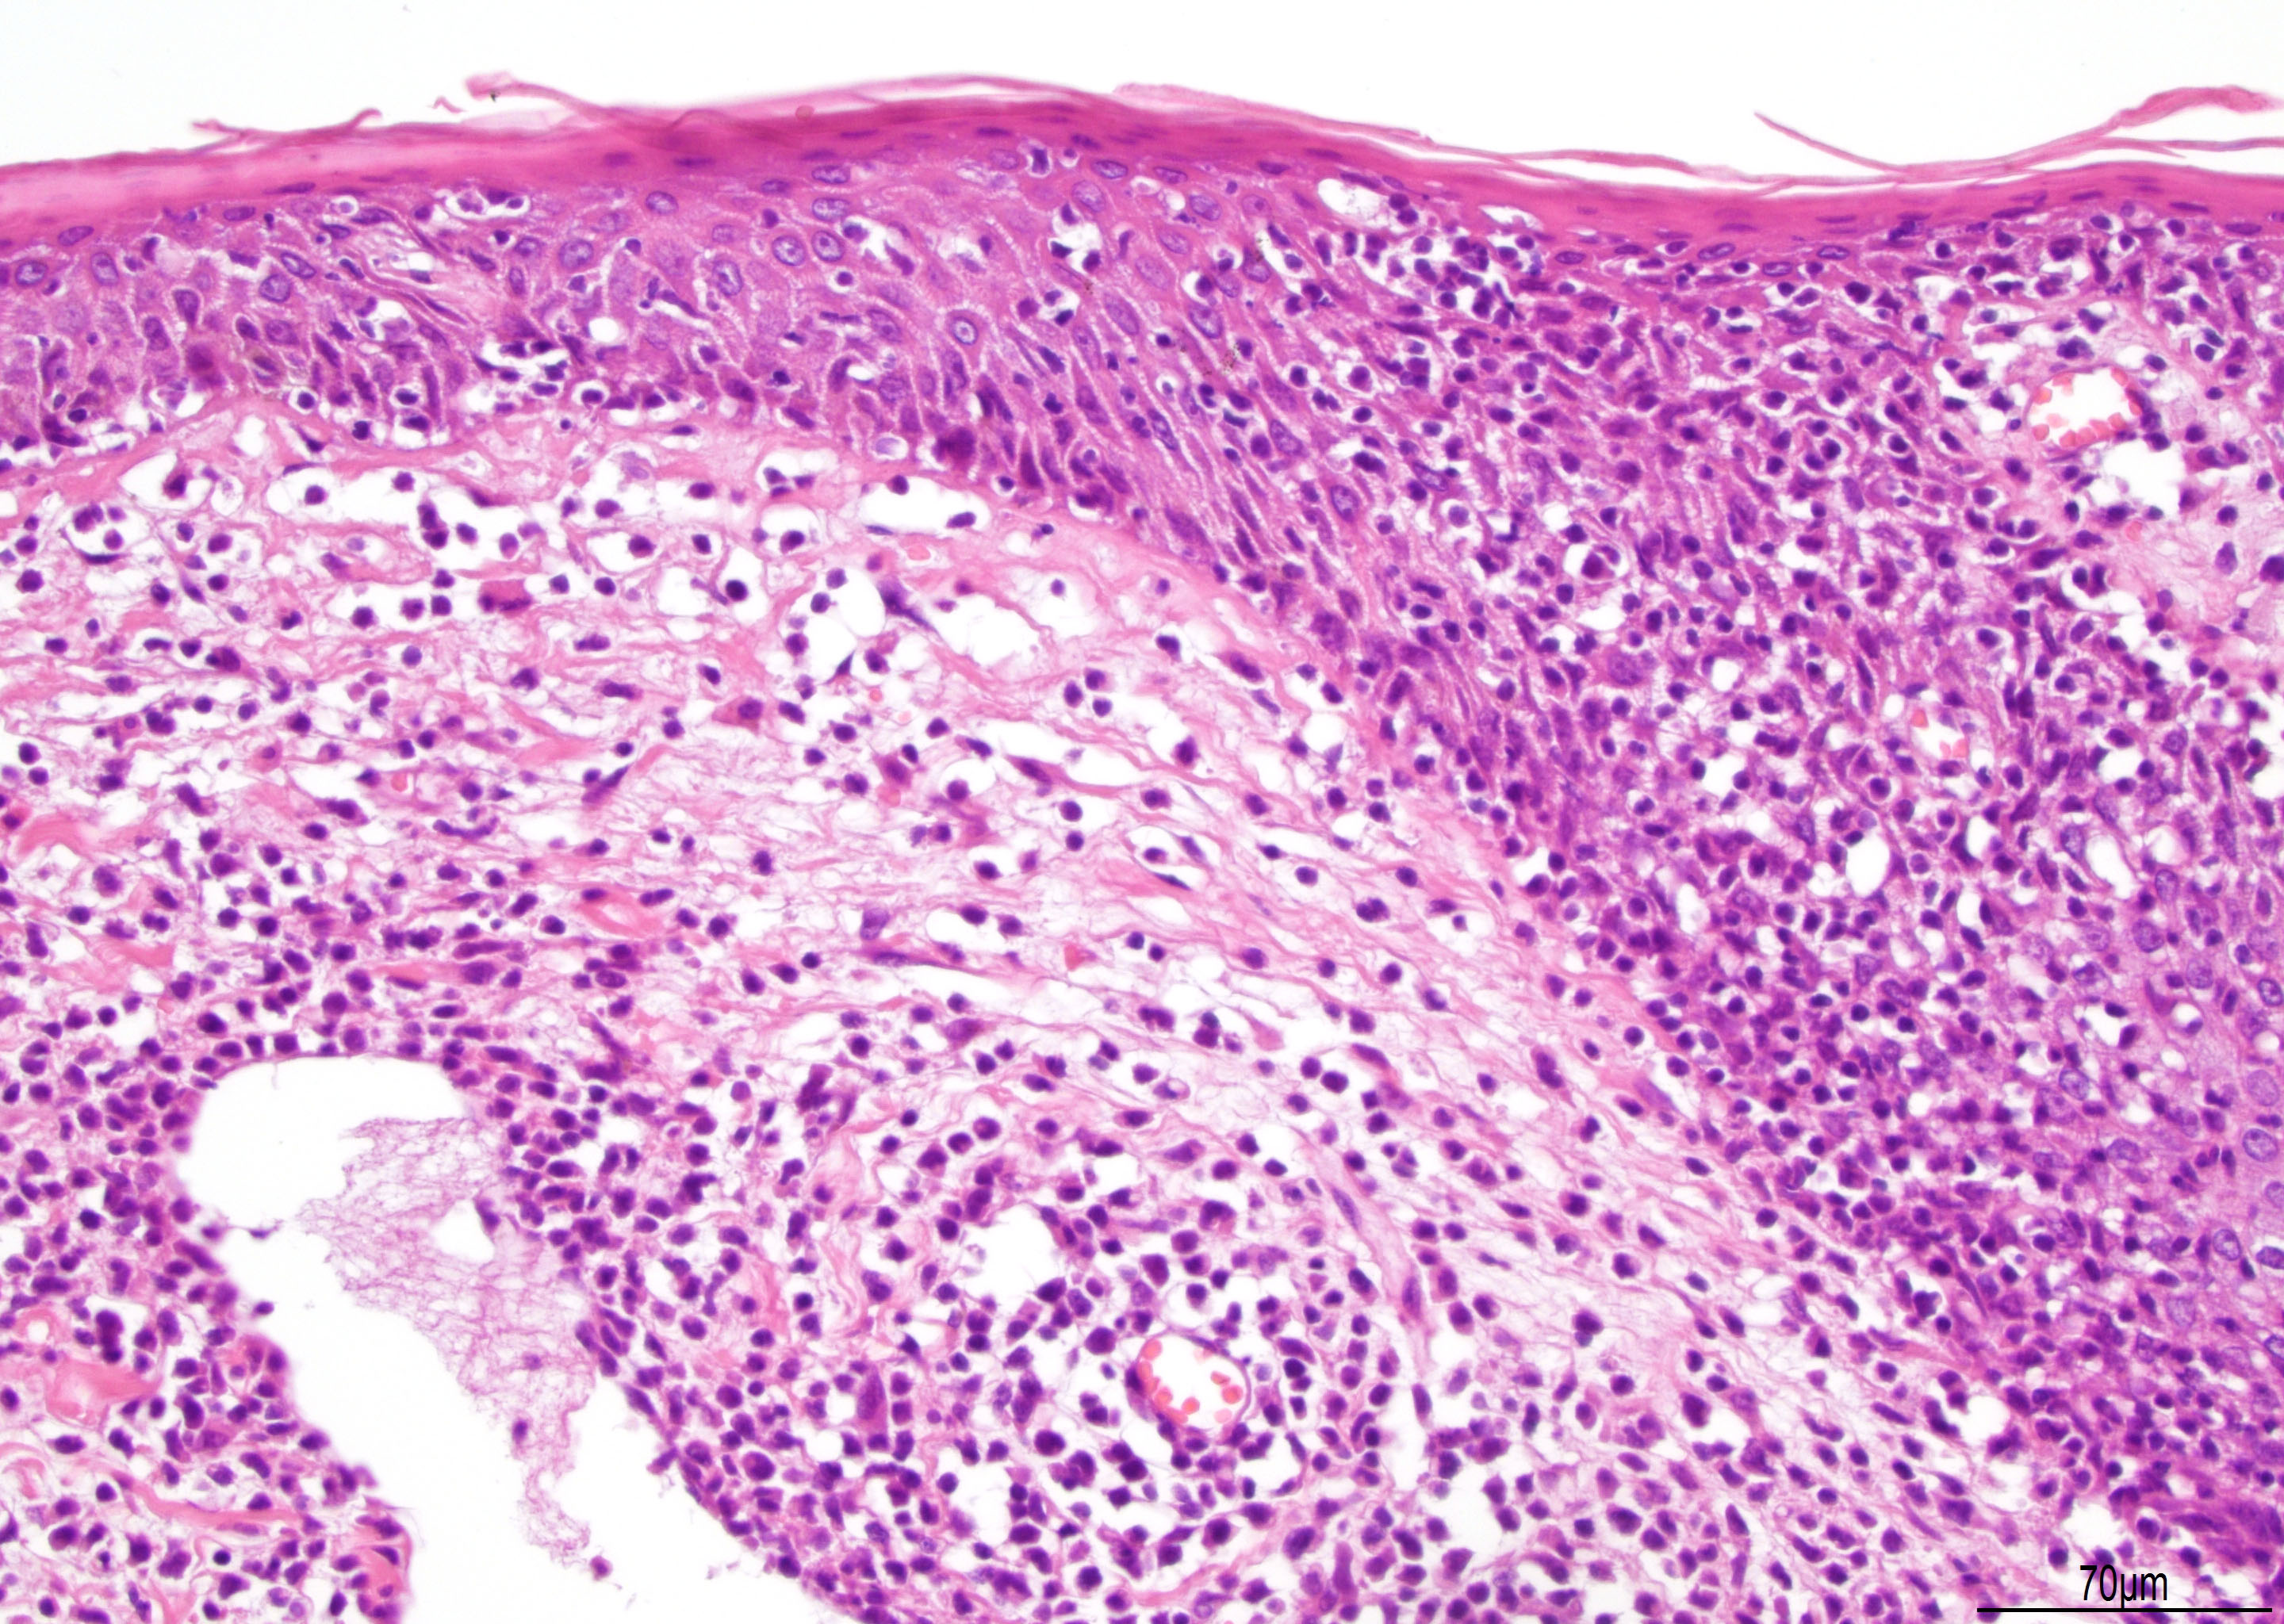

Microscopic (histologic) description

- Lymphomatoid papulosis is characterized by a wedge shaped pattern, with a wide superficial base and the tip at the bottom, usually deep dermis and less frequently into the subcutaneous tissue

- The most characteristic appearance is the presence of few to numerous large cells with a Hodgkin or Hodgkin-Reed Sternberg admixed with a reactive background of small lymphocytes and less frequently eosinophils, plasma cells and histiocytes

- The microscopic appearance and immunophenotype of large cells is variable and led to subclassification of lymphomatoid papulosis into different categories (J Am Acad Dermatol 2016;74:59, Blood 2019;133:1703, Semin Diagn Pathol 2017;34:22, J Am Acad Dermatol 2013;68:809, J Am Acad Dermatol 2012;66:928, Am J Clin Pathol 2003;119:731, Am J Surg Pathol 2010;34:1168, Am J Surg Pathol 2013;37:1)

- Type A: wedge shaped and extensive lymphoid infiltrate with neutrophils, eosinophils and histiocytes; CD30+ cells are scattered and the overall histologic appearance mimics classic Hodgkin lymphoma

Microscopic (histologic) images

Contributed by Roberto N. Miranda, M.D.